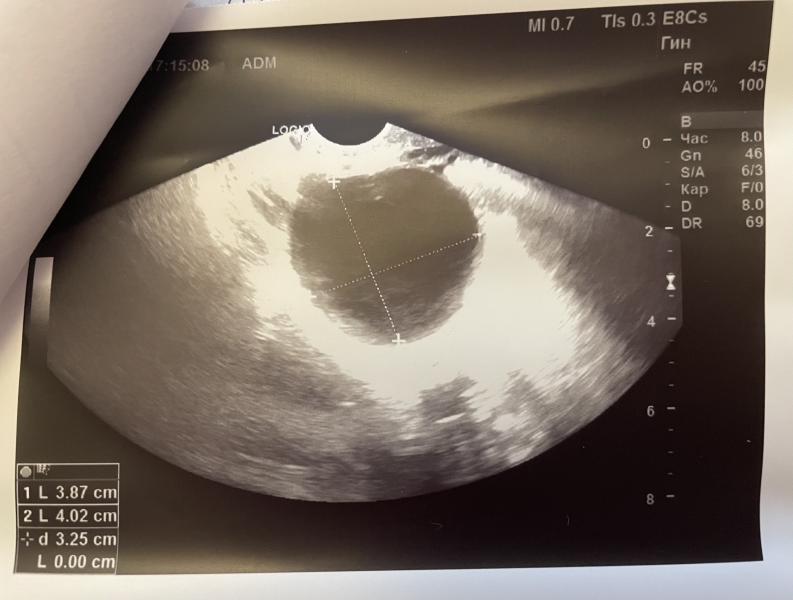

Пошла я сама в 4 недели 4 дня (23 октября) на узи в платную, чтобы исключить внематочную (боли слева внизу были). Плодное яйцо в матке, фух..но там пока ничего не видно 🙈 и киста огромная в левом яичнике, вот это то и болит 🤭🙁 и назначили дюфастон.

У вас киста как я поняла желтого тела , а в беременность часто желтое тело растёт тк работает прогестерон и его начинают называть кистой . Хорошее у вас узи , хгч у всех растёт по разному , может действительно там не один малыш , немного подождите и все будет понятно . Но причин переживать точно нет

Да, гинеколог так и сказала, что киста от этого, но меня беспокоит, что она болит 🙄

@epugacheva, она работает , и плюс давит на соседние органы и мышцы из за размера , все хорошо